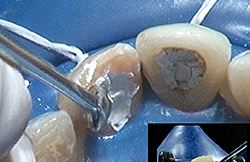

À présent nous avons une vue directe sur une large entrée canalaire où subsistent beaucoup de débris : dépôts de ciment d’obturation, excès de gutta-percha et restes d’ancien composite. « Plus la cavité sera propre et meilleure sera l’efficacité de l’éclaircissement » précise Éric Bonnet.

« Oui, pour cela j’utilise un insert Perfect Margin® que je passe aussi sur les parties de dentine très colorées » confirme René Serfaty. L’instrument passe et repasse, insiste au niveau des cornes pulpaires dont les contre-dépouilles initiales ont conservé une coloration marquée.

photo 3 - Suppression de l'excès de gutta : insert Perfect Margin® (Acteon).